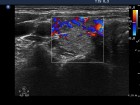

First examination (first row):

Clinical presentation: A 29-year-old woman was referred for evaluation of complaints suggesting hyperthyroidism. She had no eye signs.

Palpation: Both lobes were enlarged. No nodule was palpable.

Ultrasonography: Both lobes were enlarged, moderately hypoechogenic, inhomogeneous and displayed increased vascularization.

Diagnosis: Graves' hyperthyroidism.